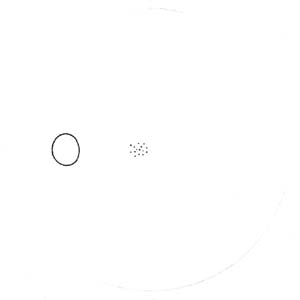

Buňky v centrální části sítnice se začínají diferencovat nejdříve a již za týden jejich výběžky dosahují až k terči. Tak vzniká základ makulopapilárního svazku. Během dalších několika dnů se diferencují gangliové buňky v perifernějších oblastech sítnice. Těm, které rostou z temporální strany, překáží v cestě ke zrakovému nervu již vytvořený makulopapilární svazek a musí jej obloukovitě obejít. Vlákna rostoucí z gangliových buněk z nasální strany takovou překážku na cestě nemají a jejich průběh ke zrakovému je přímý. Tímto způsobem během několika dní vzniká vrstva nervových vláken. Její uspořádání nám umožňuje pochopit lokalizaci skotomů zorného pole.

Výpadky nervových vláken na sítnici a graficky na perimetru podle Minclera

Korelace lokálního výpadku nervových vláken se změnami zorného pole dle Minclera

Výpadek zorného pole u glaukomu poprvé popsal Albrecht von Graefe roku 1856. Na přelomu 19. a 20 století byly popsány lokalizované výpadky zorného pole Bjerumem a Rennem.

Když exkavace zasahuje až okraji terče dochází k poškození vláken, která vedou až do temporální části sítnice k tělům gangliových buněk, uloženým v sousedství horizontálního švu. Poškození těchto buněk a jejich axonů se projeví nasálním skokem s arkuátním Bjerumovým skotomem.

Pokud exkavace nedosahuje k samému okraji terče (miskovité exkavace), svědčí to pro poškození vláken z povrchnější vrstvy, které směřují k gangliovým buňkám uloženým paracentrálně – periferně od makulopapilárního svazečku. Poškození těchto buněk a jejich axonů se projeví paracentrálními skotomy.